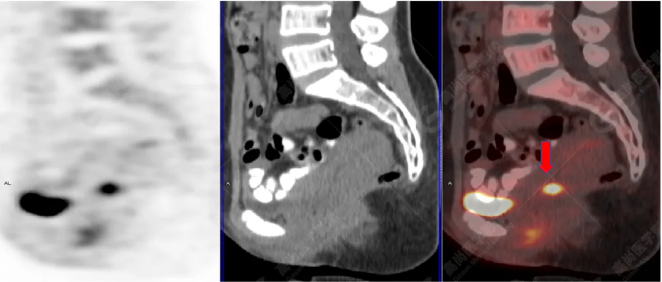

病史摘要:女性 36歲 因左后肋區(qū)疼痛1月余查體,無其他不適。PET/CT影像圖

左胸一后肋溶骨性骨質(zhì)破壞,周圍伴軟組織形成,F(xiàn)DG代謝增高,SUVmax為10.9。

找到引起骨痛病灶,病因:原發(fā)?轉(zhuǎn)移?感染?

最終診斷:宮頸癌伴肋骨單發(fā)骨轉(zhuǎn)移。